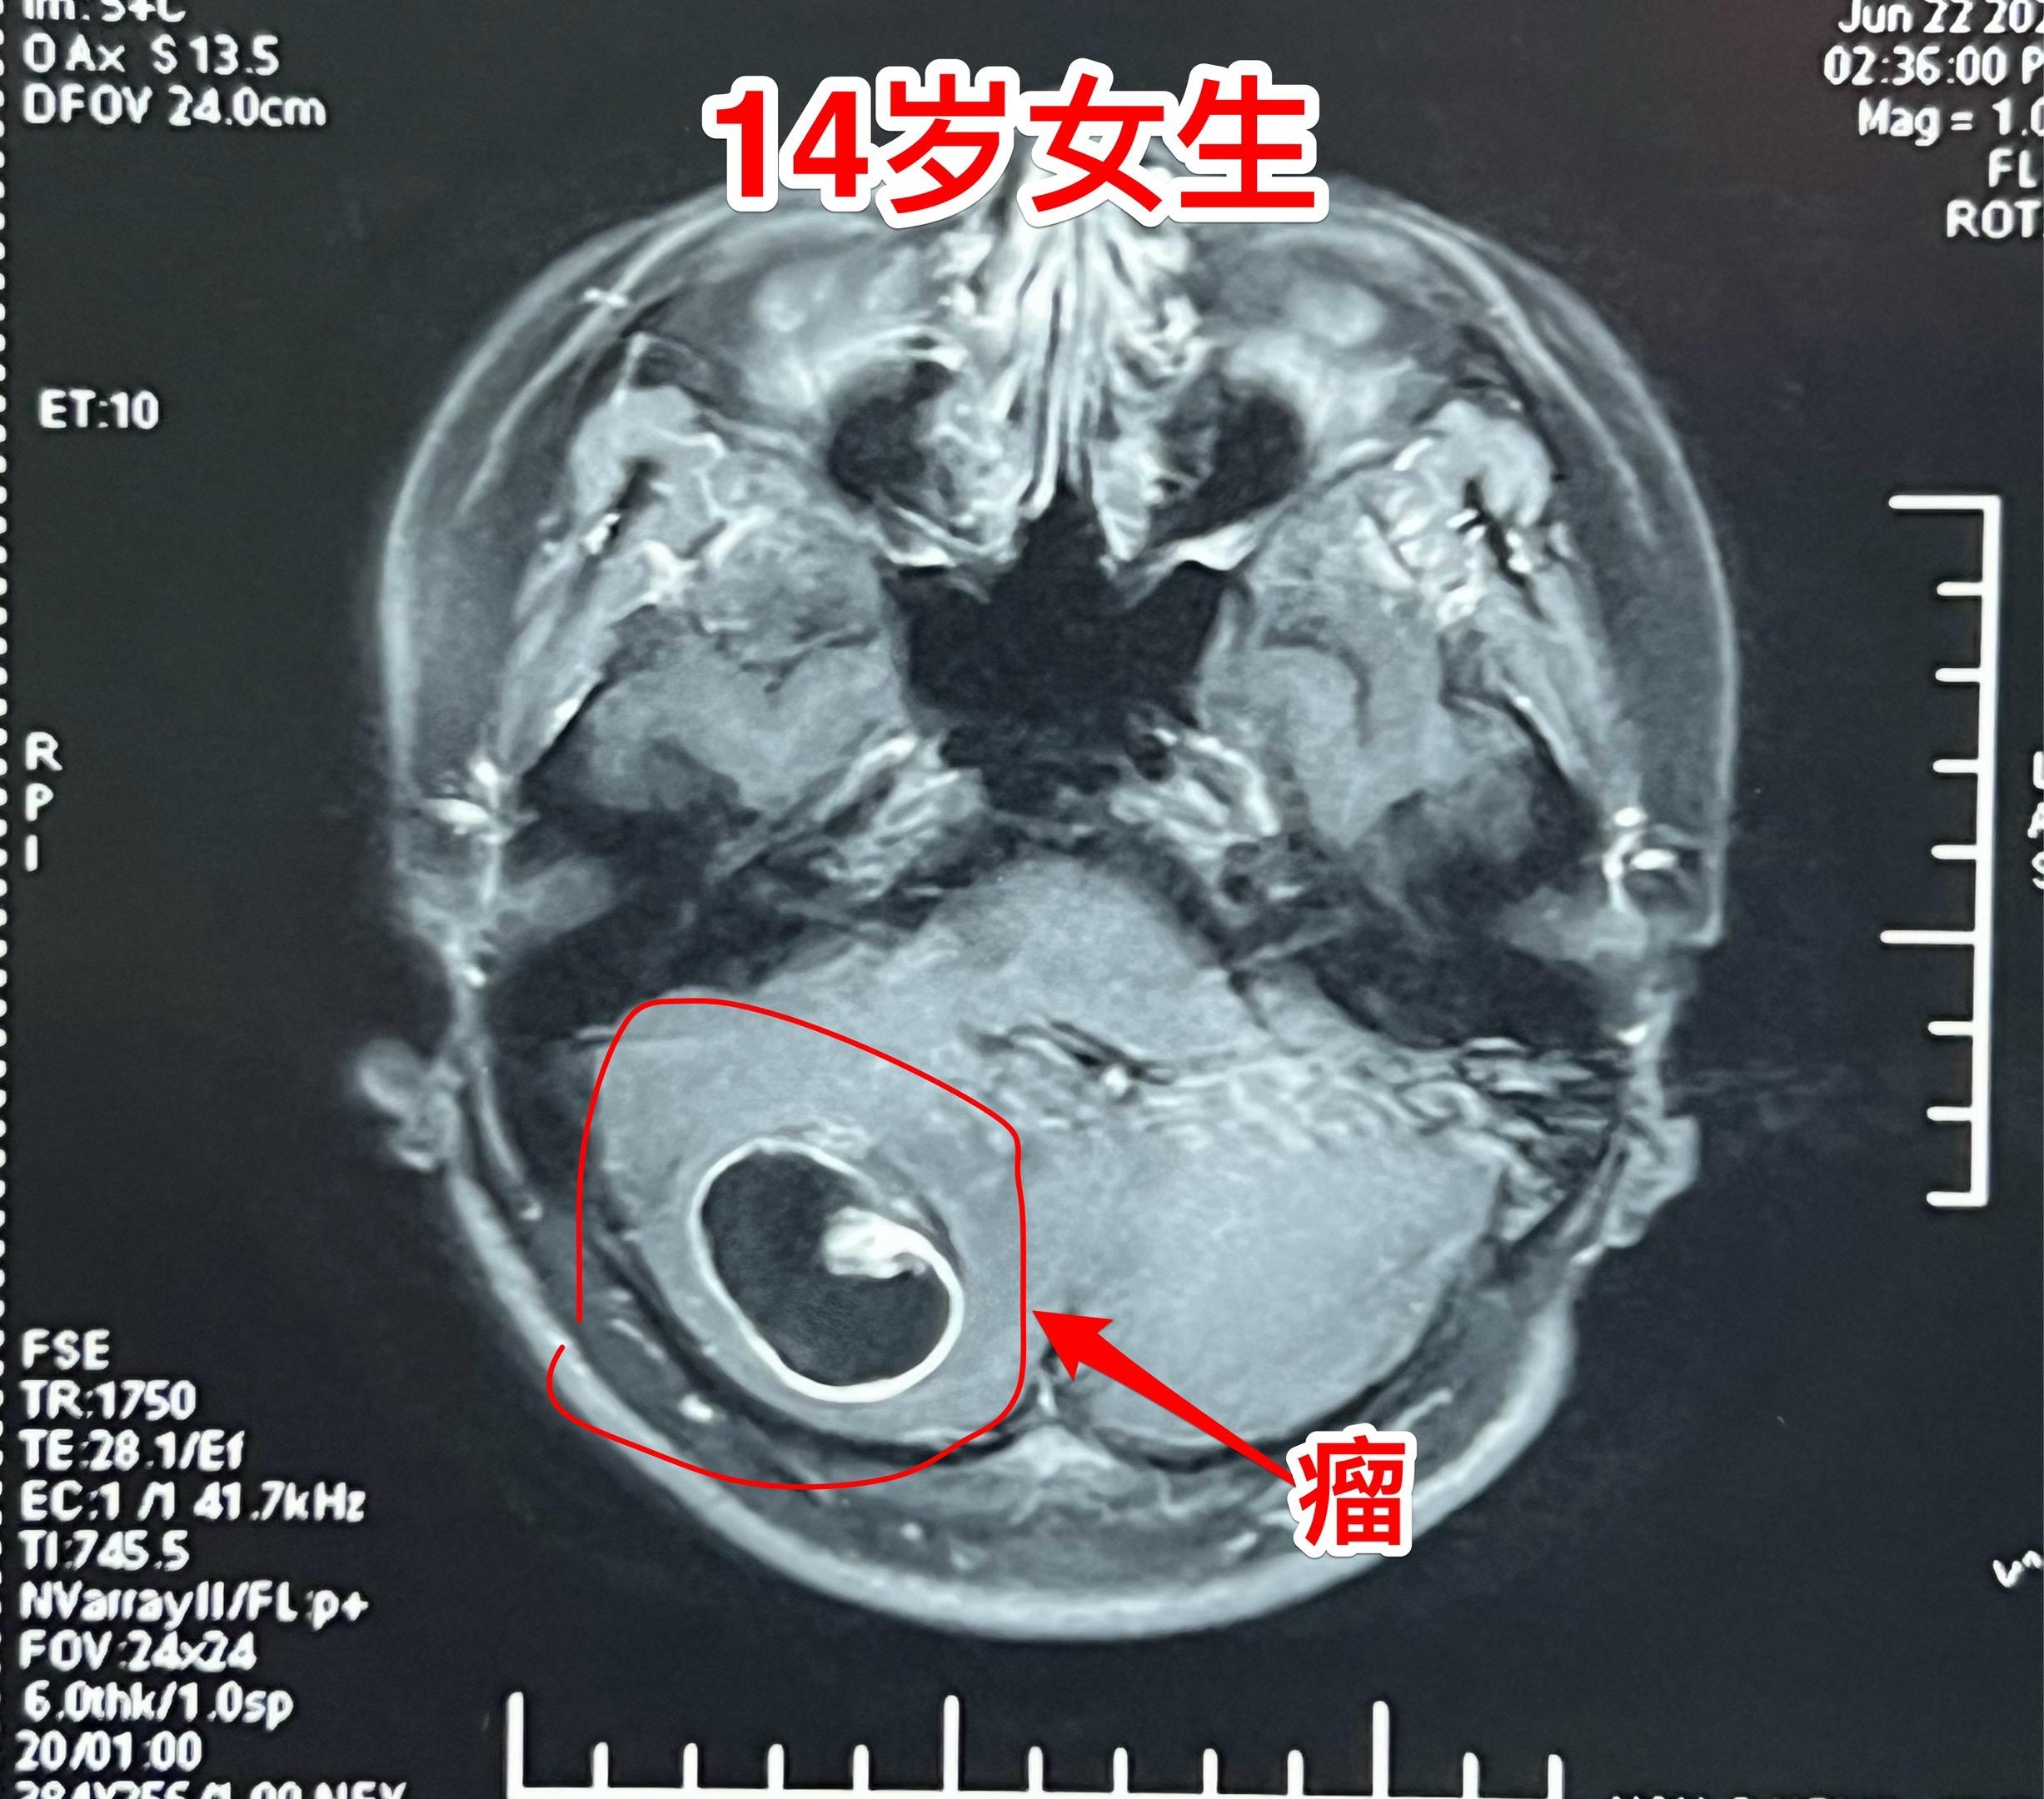

小孩子脑肿瘤中最常见的是小脑肿瘤。与大人相比,小孩子一般是不容易患上肿瘤性疾病的。然而,小孩子也会患上肿瘤性疾病,其中包括脑部肿瘤、白血病、骨肿瘤等等。 小孩子的脑肿瘤中最常见的小脑肿瘤,小脑肿瘤经常导致病人呕吐。所以,小孩子在没有感冒症状的前提下出现反复呕吐症状,要想到脑部是不是出了问题? 这个14岁沧州女生平常身体很健康,近5天感觉头晕、恶心、呕吐,在当地医院就医,行脑部磁共振、CT检查发现了小脑肿瘤。用甘露醇降颅压后她的症状明显减轻了。6月27日下午到我科来住院,6月2